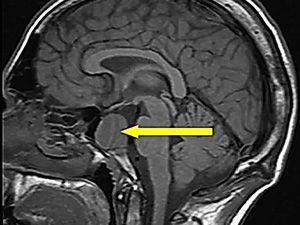

КТ гипофиза

Компьютерная томография гипофиза — это инструментальный рентгенологический метод диагностики, направленный на выявление новообразований этого мозгового придатка.

КТ гипофиза с контрастом в высоком разрешении позволяет сделать исследование максимально эффективным и получить всю необходимую информацию для того, чтобы поставить диагноз и назначить адекватное лечение. Цена КТ гипофиза в клинике ЦЭЛТ представлена на соответствующей странице нашего сайта с прейскурантом услуг. Её можно всегда уточнить, позвонив нам.